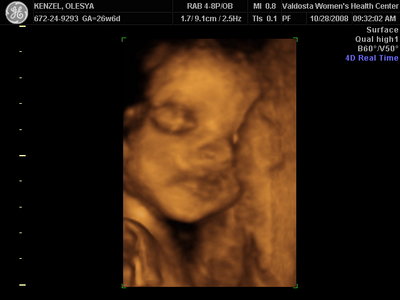

Ксюнь, а мы вообще не поняли. Она на всех фотках разная, да еще размытость такая. Пуповина то на носу болталась, то руками-ногами закрывалась. Главное что четкости нет совсем. Лоб у мужа тоже большой, а носы и губы зачастую на 3Д-4Д выходят разамазанно-пухло-приплюснутыми Поставлю для наглядности фотку моей средней-Джианки с 3Д УЗИ, там видно черты намного лучше и она на себя ту похожа сейчас, хотя родилась мне совсем на фото УЗИ не казалась похожей.

| Вложения: |

KENZEL,OLESYA_3.JPG [ 56.84 КБ | Просмотров: 1428 ]

Катюш, какой прикольный бутузик ! Олесь, после фотки средней - точно прям похожи!